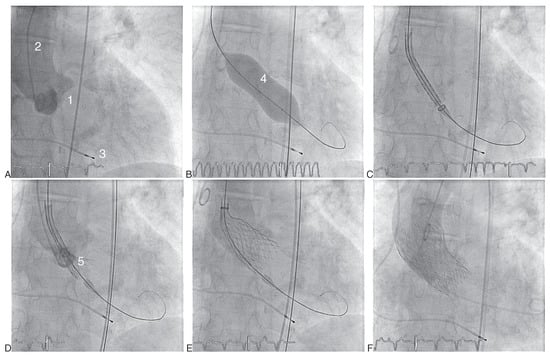

Abbildung 3. Transapikale Implantation einer Edwards-Sapien-Bioprothese (AE). (A) Aortographie. (B) Vordilatation unter rapid pacing. (C) Positionierung der auf den Einführungskatheter geladenen Bioprothese. (D) Klappenimplantation mittels Ballon-Inflation unter rapid pacing. (E) Kontrollangiographie nach Implantation. 1 Transösophageale Echokardiographie-Sonde; 2 Pigtail-Katheter; 3 Aortenklappenannulus; 4 transapikale Einführungsschleuse; 5 Edwards-Ballon zur Vordilatation der Aortenklappenstenose; 6 Edwards-SAPIEN-Klappe geladen auf Einführungskatheter; 7 Entfaltete Prothese mit Implantationsballon; 8 Implantierte Aortenklappenprothese nach Zurückziehen des Implantationsballones.